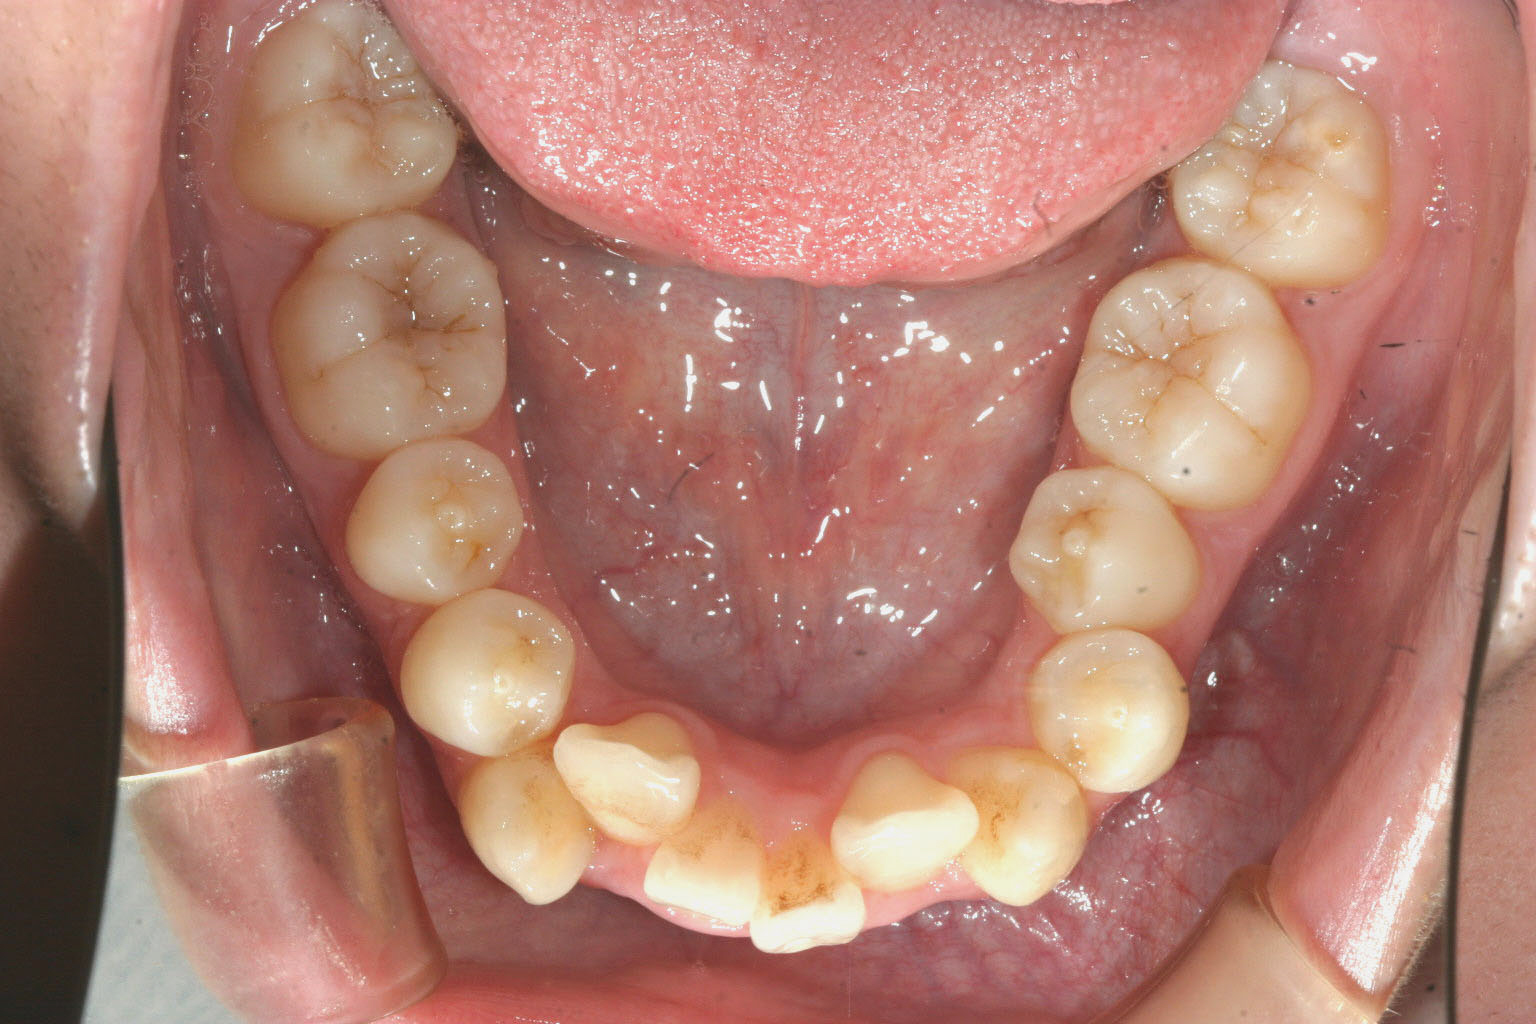

歯列が狭い為にしわ寄せが前歯に現れ、かなりの出っ歯になっています。

下顎もアーチが狭く前歯がガタガタになっています。

前歯の前突が目立ちます。